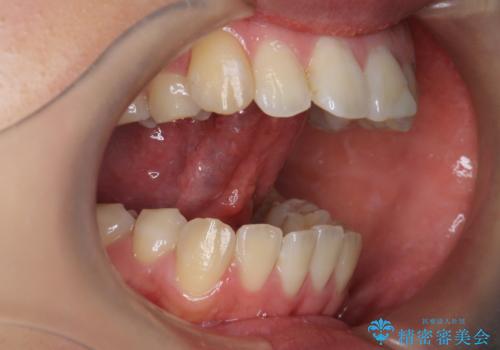

舌が持ち上がらない 舌小帯切除

- 舌小帯の切除を希望して来院。

舌を持ち上げた時に、ハート型になるのが適応症です。